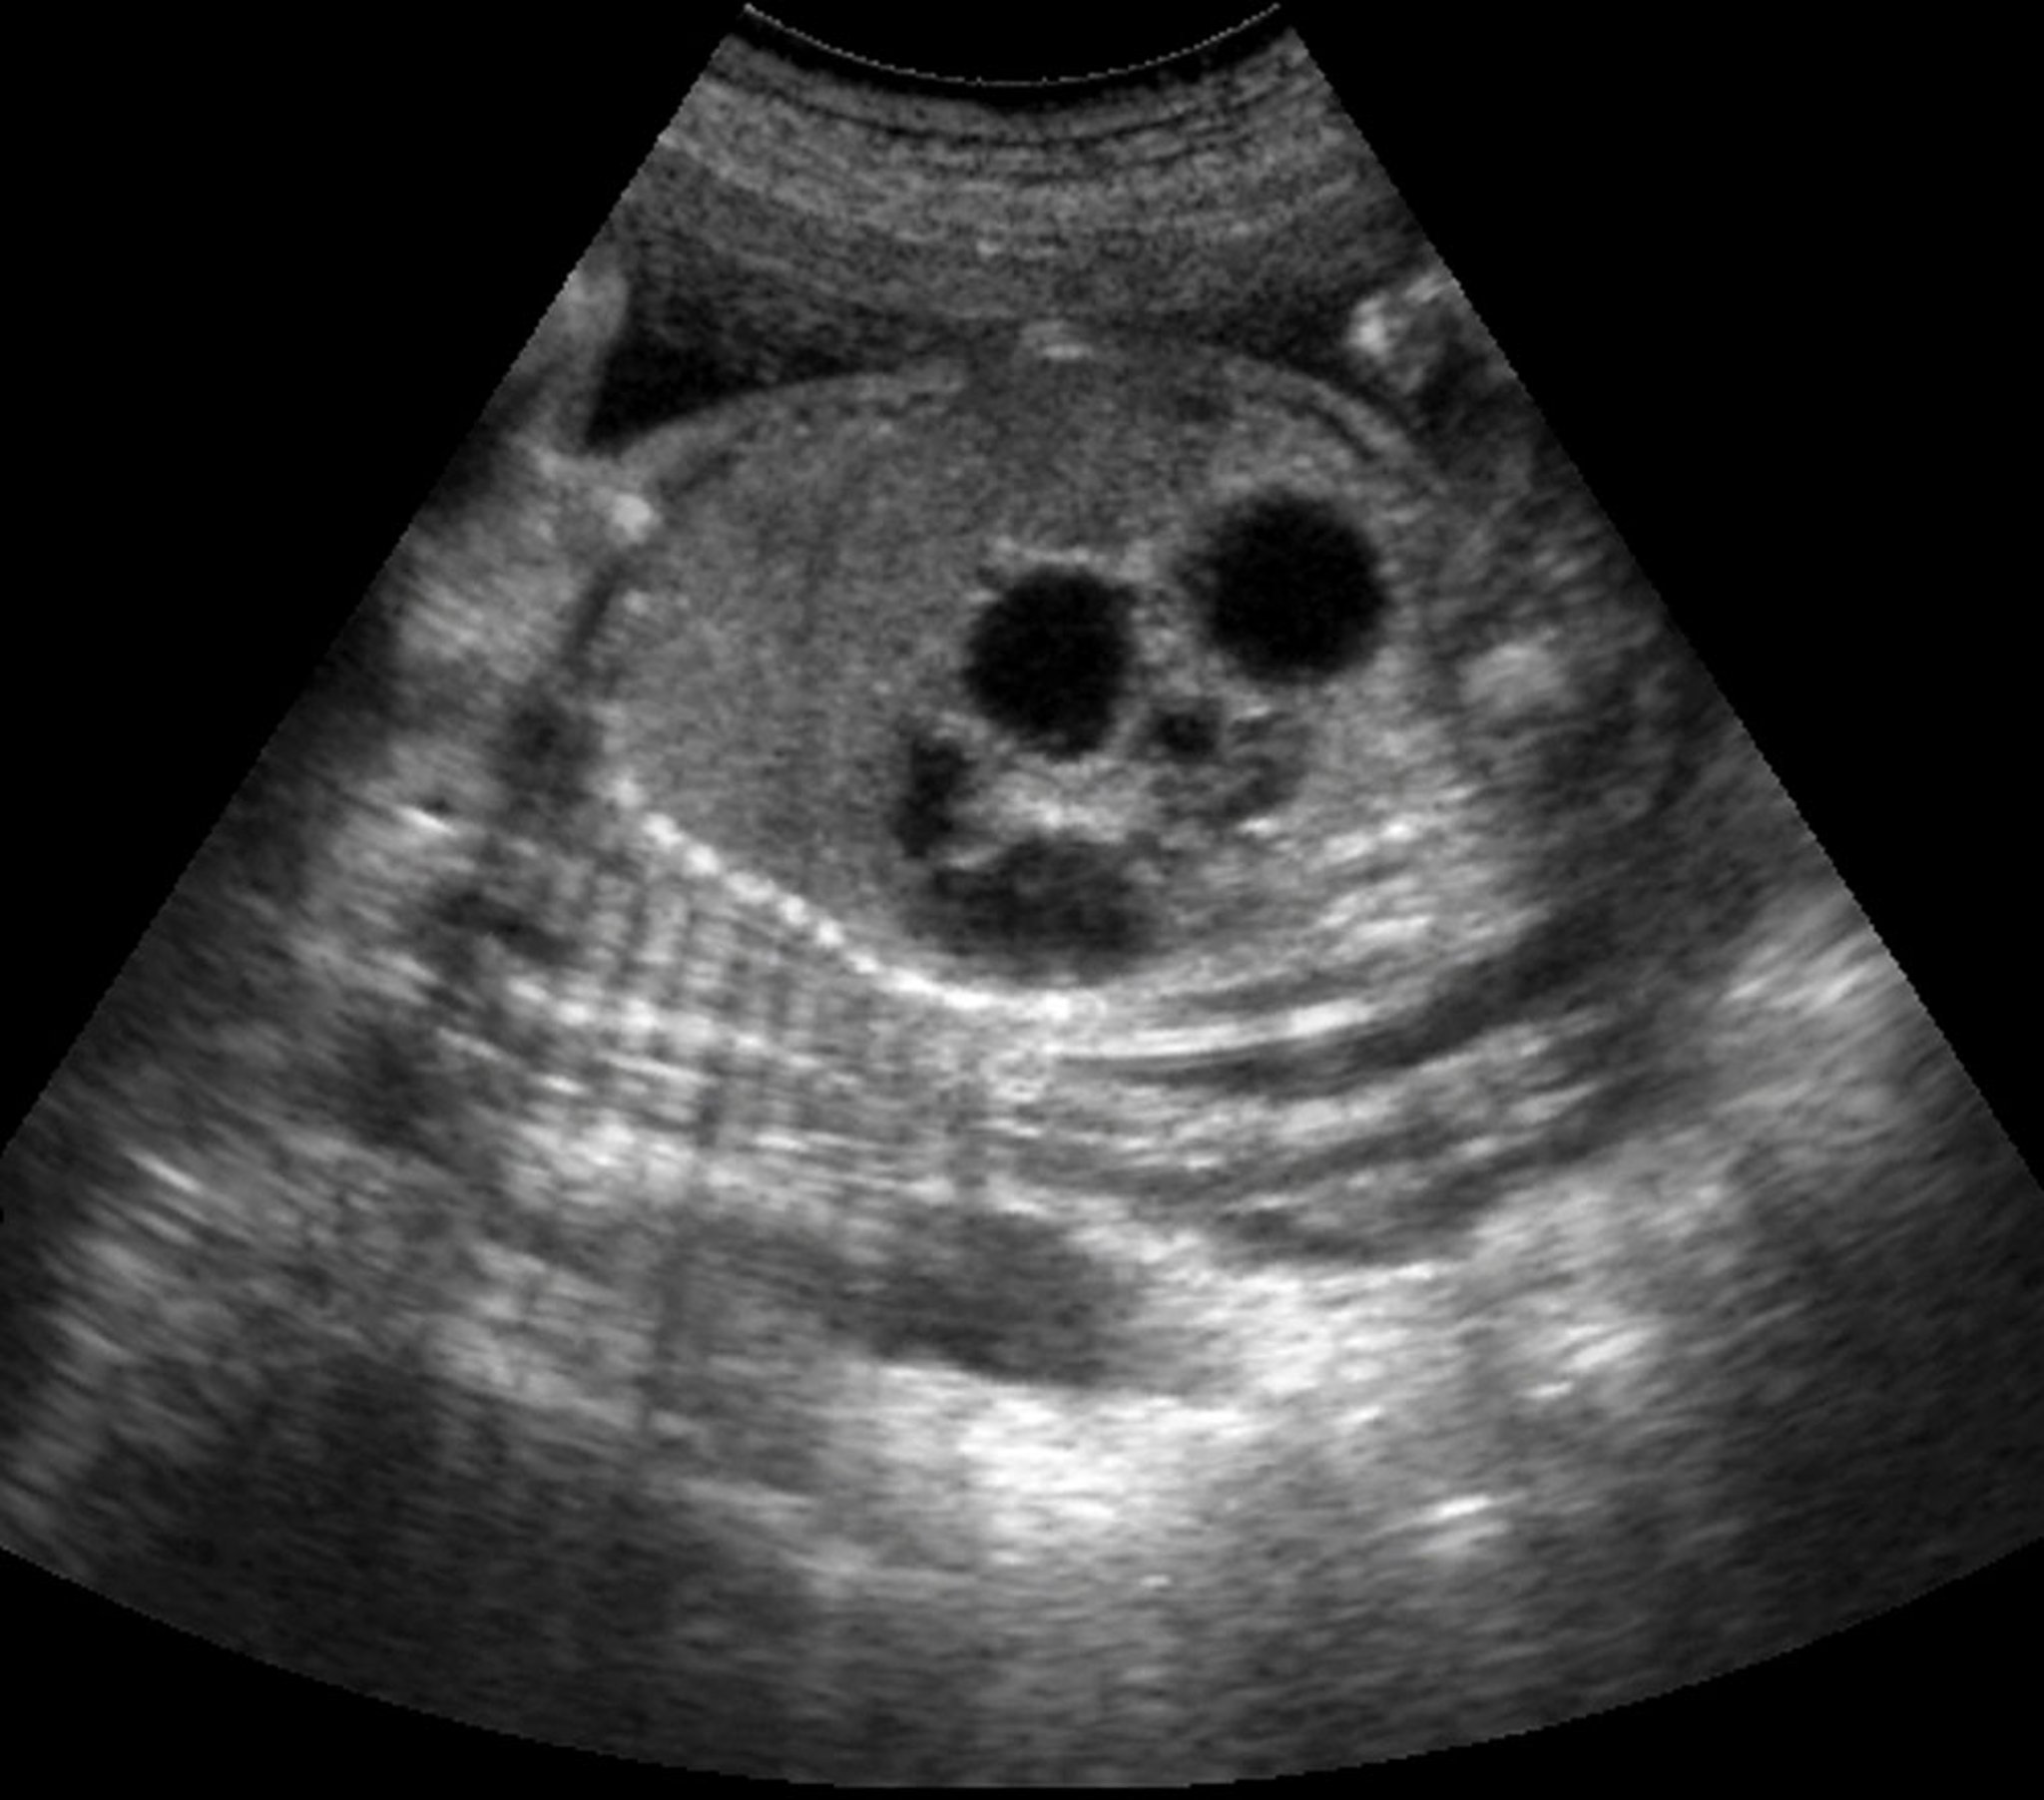

Le diagnostic d'atrésie duodénale est suspecté avant la naissance en cas d'hydramnios et/ou de dilatation de l'estomac. L'échographie prénatale peut détecter un signe de bulle double (une grande bulle gastrique et une plus petite bulle duodénale proximale) dans jusqu'à 80% des cas (2).

Cette échographie montre le signe de la double bulle chez un fœtus avec atrésie duodénale.

Cette radiographie montre le signe de double bulle typique observé en cas d'obstruction duodénale complète. La petite bulle représente le duodénum dilaté proximal (flèche blanche); la grande bulle représente l'estomac (flèche noire). Ce signe peut être observé en cas d'atrésie duodénale, de diaphragme duodénal, de pancréas annulaire et de veine porte préduodénale. Rarement, il peut également être observé en cas d'obstruction duodénale complète résultant de bandes de Ladd chez un patient qui a une malrotation.